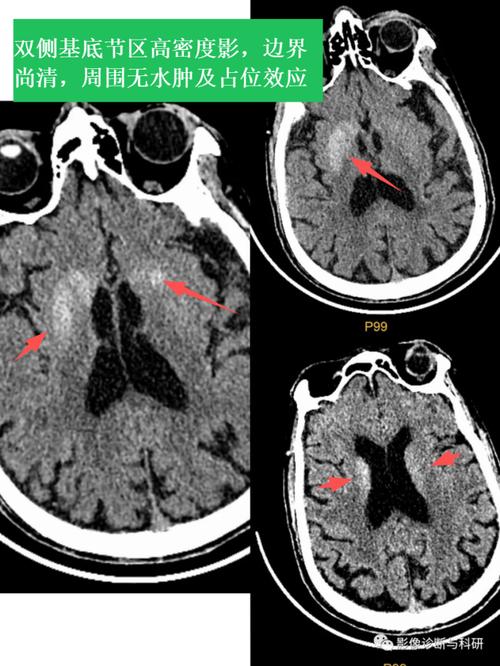

(图片来源网络,侵删)